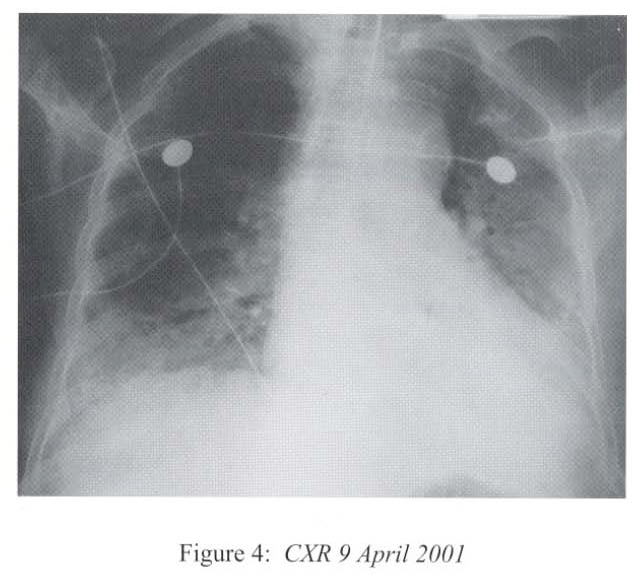

The respirology team was consulted at this time and we took over the case and managed her in the High Dependency Unit. The differential diagnoses included uncontrolled bacterial or fungal pneumonia, Pneumocystis carinii pneumonitis, viral pneumonitis, autoimmune pneumonitis, massive pulmonary embolism and massive pulmonary haemorrhage. She was treated with broad-spectrum antibiotics (piperacillin/tazobactam, amikacin) together with intravenous gancyclovir and cotrimoxazole. Supportive treatment included inotropes infusion, peritoneal dialysis, parenteral nutrition, and optimization of mechanical ventilation. Hydrocortisone was continued since she has been on systemic steroid for 3 months and the haemodynamic state was unstable. Bronchoscopy via the endotracheal tube showed copious mucoid secretions arising from both lung bases, and there was patchy mucosal excoriations involving the lower lobes. There was no sign of pulmonary haemorrhage. No transbronchial biopsy was attempted as she was on positive pressure ventilation and in critical state. CXR after bronchoscopy showed rapid resolution of pneumonia shadows in multiple areas (Figure 4).

Radiological features are also diverse and variable 15,16.On the chest radiograph, early signs include miliary shadows, diffuse reticular interstitial opacities, patchy alveolar opacities, segmental or lobar opacities. In the advanced stage, there can be extensive airspace shadows affecting both lungs, with occasional pleural or pericardial effusion. Without treatment, ARDS quickly evolves. Rarely, ARDS develops after antihelminthic treatment due to release of toxic breakdown products 17.On the abdominal radiograph, there can be thickened mucosal folds, segmental small bowel dilatation or perforation. Among all these variable radiological features, a characteristic pattern of Strongyloides hyperinfection has been described by the radiologists of Hong Kong, which consist of fleeting and rapidly changing CXR signs, predominant small bowel abnormality on AXR, and close temporal relationship of CXR & AXR signsl8. Detection of larvae in stool or other specimens is difficult (Table 1). Serological diagnosis19 is an attractive alternative but it is not available in Hong Kong.

Radiological features are also diverse and variable 15,16.On the chest radiograph, early signs include miliary shadows, diffuse reticular interstitial opacities, patchy alveolar opacities, segmental or lobar opacities. In the advanced stage, there can be extensive airspace shadows affecting both lungs, with occasional pleural or pericardial effusion. Without treatment, ARDS quickly evolves. Rarely, ARDS develops after antihelminthic treatment due to release of toxic breakdown products 17.On the abdominal radiograph, there can be thickened mucosal folds, segmental small bowel dilatation or perforation. Among all these variable radiological features, a characteristic pattern of Strongyloides hyperinfection has been described by the radiologists of Hong Kong, which consist of fleeting and rapidly changing CXR signs, predominant small bowel abnormality on AXR, and close temporal relationship of CXR & AXR signsl8. Detection of larvae in stool or other specimens is difficult (Table 1). Serological diagnosis19 is an attractive alternative but it is not available in Hong Kong.